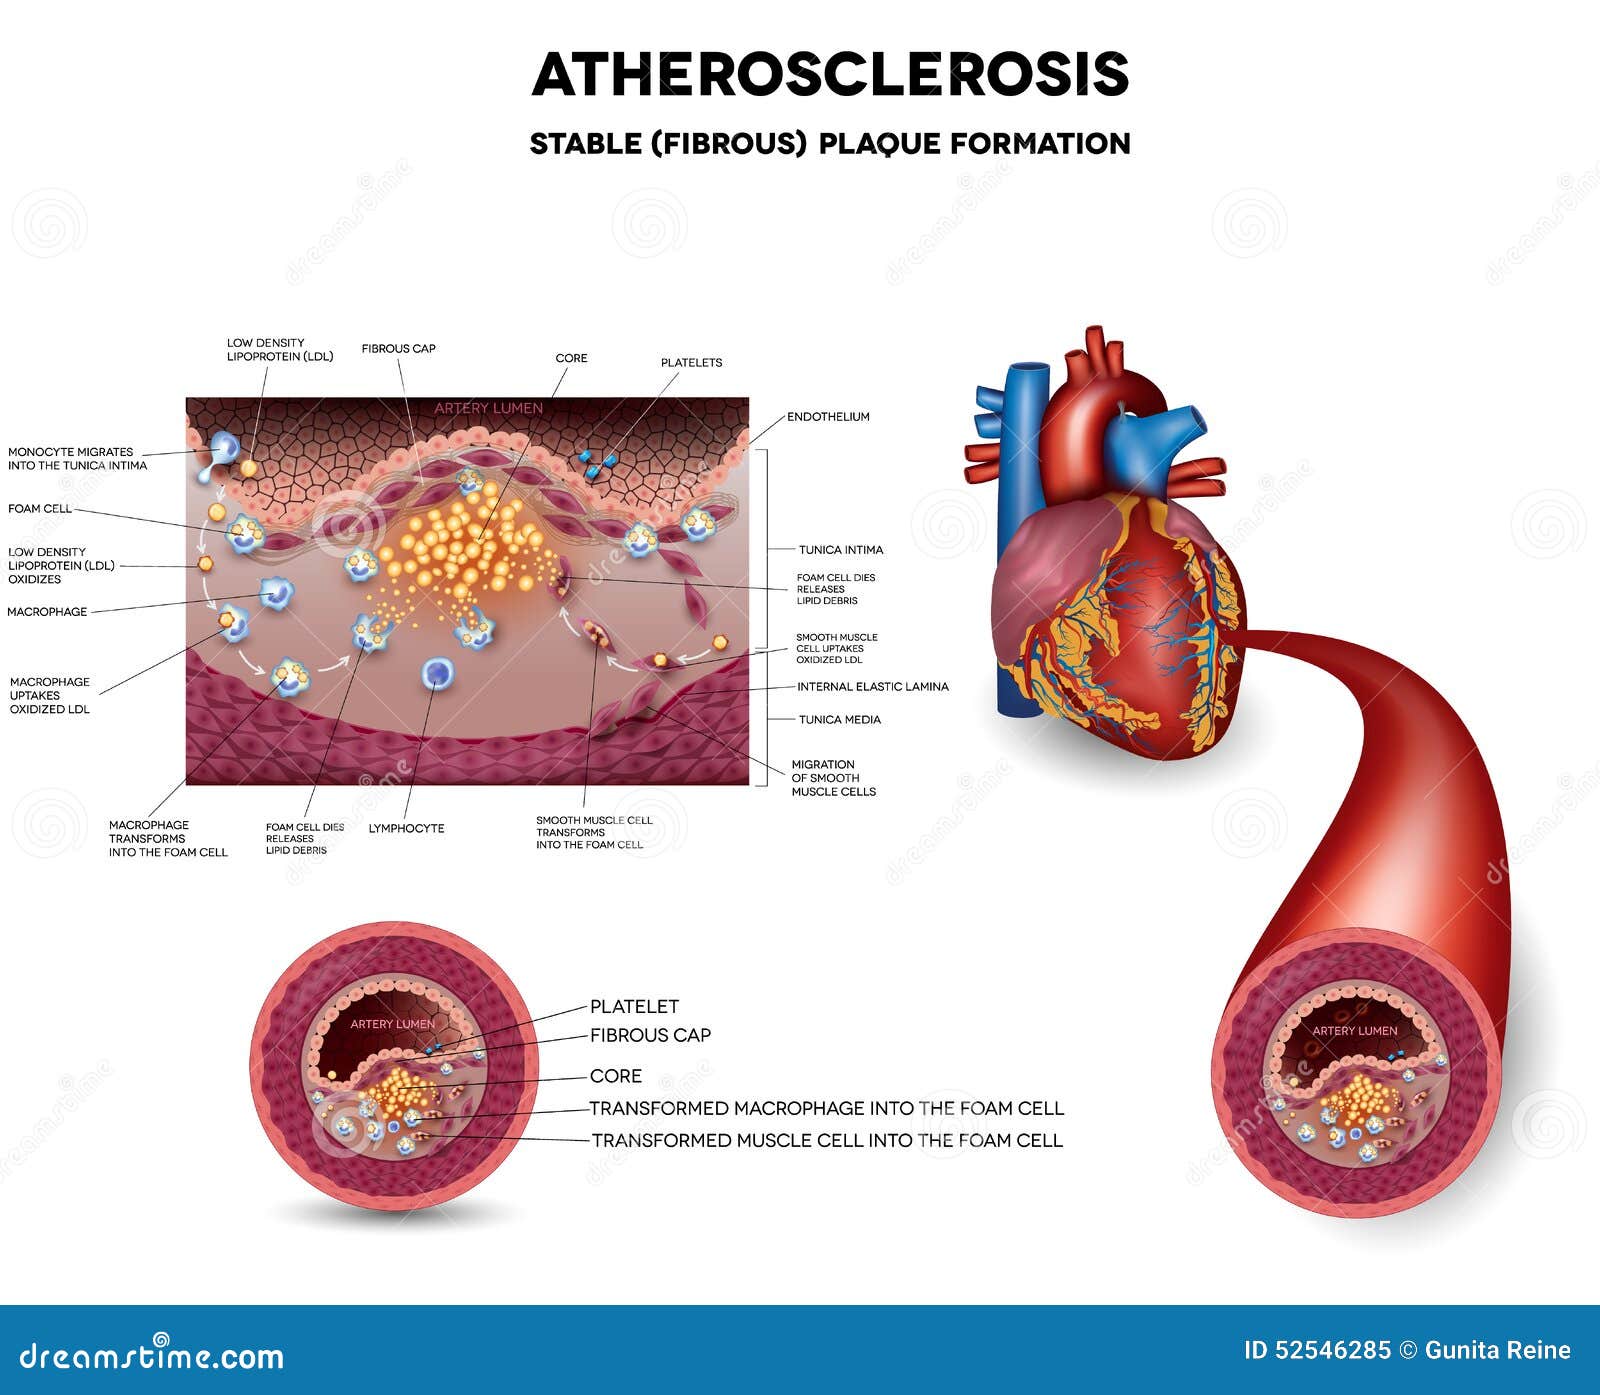

Atherosclerosis. Fibrous Plaque Formation Stock Vector – Image: 52546285

Atherosclerosis | Linus Pauling Institute | Oregon State University

Atherosclerosis stock vector. Illustration of cardiovascular – 39305436

Arteriosclerosis / atherosclerosis – Symptoms and causes – Mayo Clinic

Atherosclerosis stages. Normal functions, endothelia disfunction …